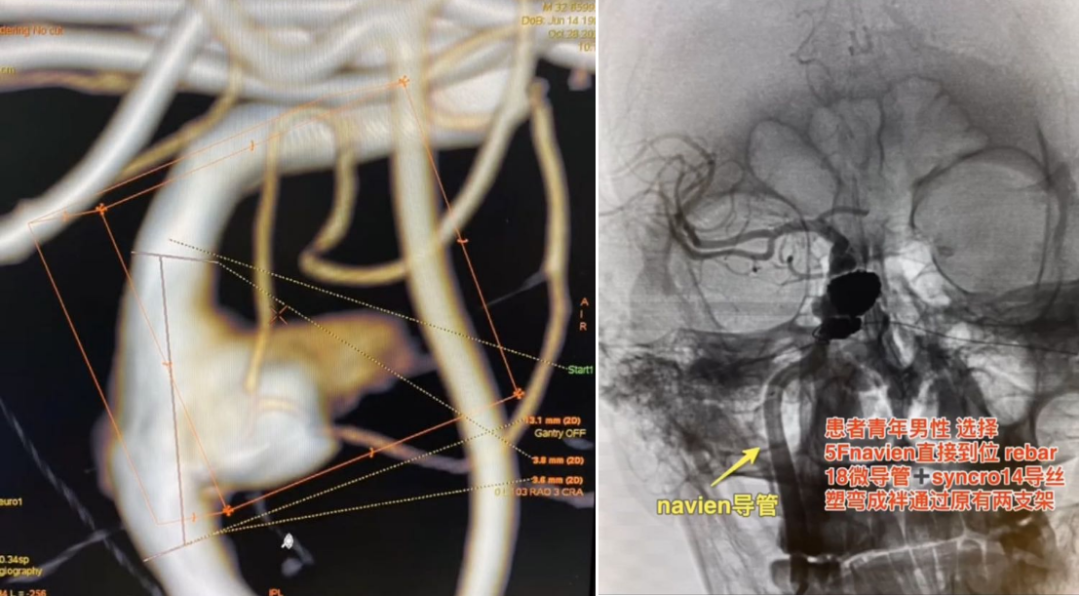

时全星教授:tubridge03治疗颈内动脉c3-c4段多发大动脉瘤一例

图片尺寸1080x581